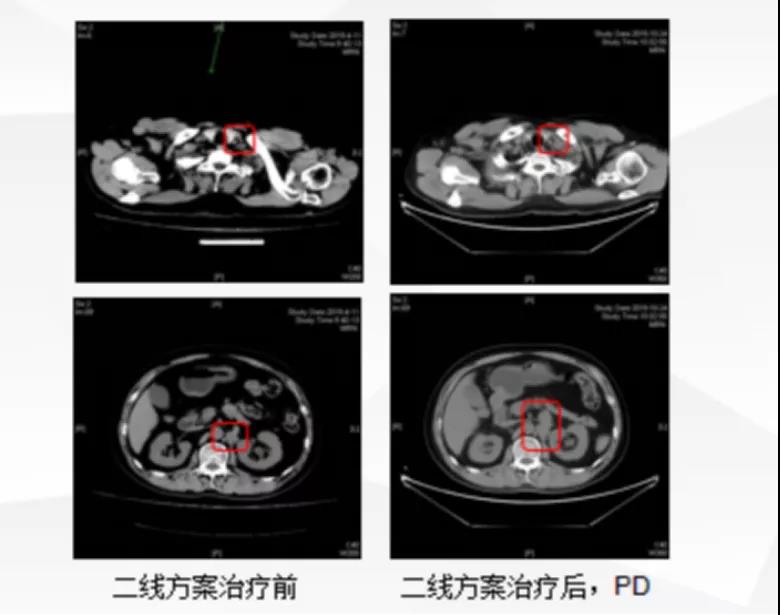

二线治疗 2019-04-12至9-18单药白蛋白结合紫杉醇200mgd1,8化疗6周期,CT疗效评估稳定(SD)。2019-10-24 CT示左侧锁骨上及腹膜后多发肿大淋巴结较前增大, MSI检测为MSS。